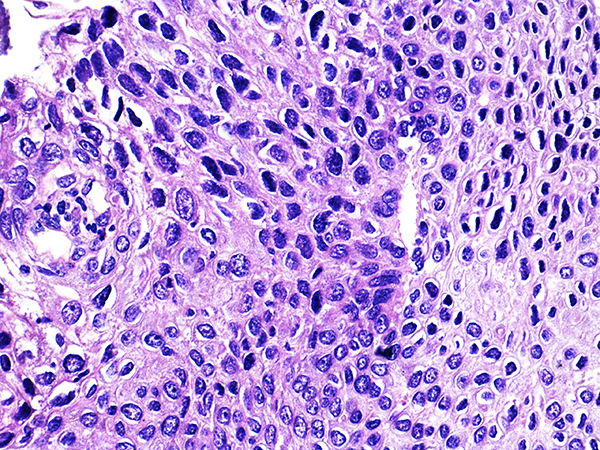

Area 1 - Soft Bx CIN 2 40x - High Power |

![]() Case 1